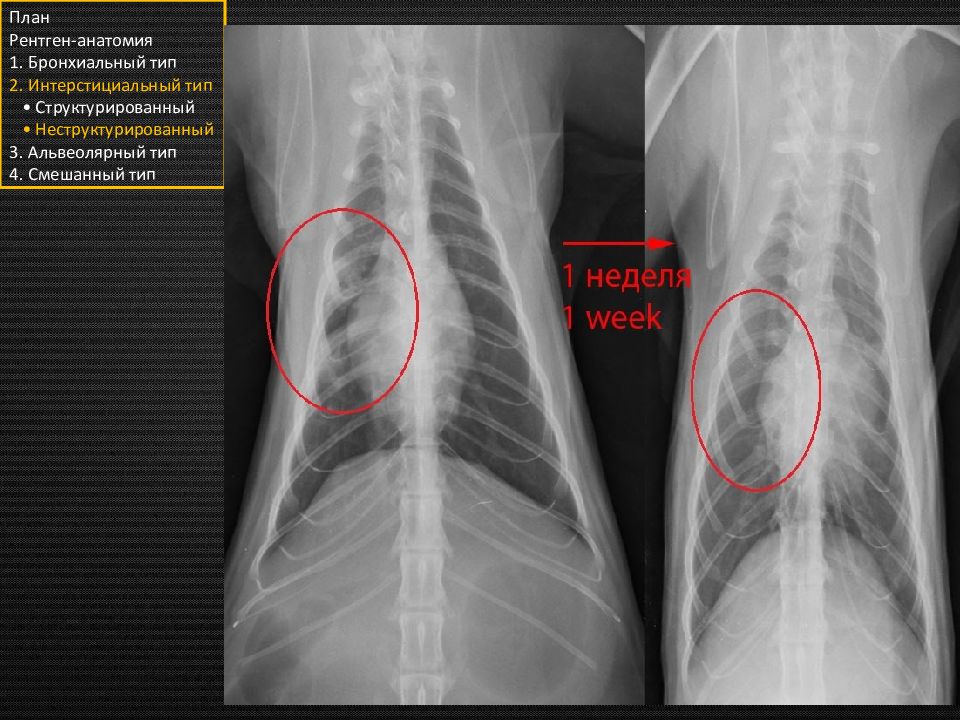

Этот подтип назван неструктурированным, так как не имеет чётких границ и неоднороден. То есть будут некоторые затемнения в лёгких, через которые мы будем видеть долевые сосуды, кости, сердечный силуэт и прочие структуры. План Рентген-анатомия 1. Бронхиальный тип 2. Интерстициальный тип • Структурированный • Неструктурированный 3. Альвеолярный тип 4. Смешанный тип «туман» «вата» «облака»